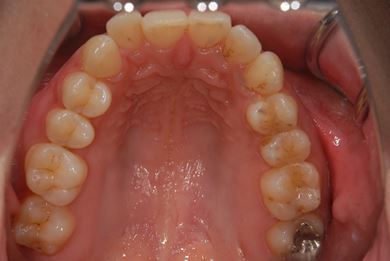

| 性別/年齢 | 女性 / 30歳 | ||||||||||||||||||||||||||||||||

| 主訴 | 銀歯がはずれた奥歯にひびが入っており、抜歯しなければいけないため、インプラントの治療相談を希望。 | ||||||||||||||||||||||||||||||||

| 治療内容 | インプラント1本、メタルボンドセラミック1本 | ||||||||||||||||||||||||||||||||